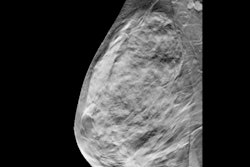

Benign breast disease refers to noncancerous breast lumps, cysts, or nipple discharge. While this is a common condition for women, it is considered a risk factor for breast cancer in women. Higher breast density found on mammography is another risk factor.

The researchers found that breast cancer risk was 1.36% in women with fatty breast tissue and 3.2% in women with extremely dense breasts.

They also found that women with extremely dense breasts and benign breast disease had the greatest risk of breast cancer, as indicated in the table below.